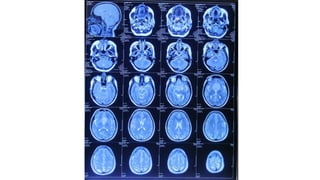

Radiological findings

• Multiplaner sagital ,coronal and axial images show a well defined ,midline, broad dural based,

Radiological findings • Multiplanersagital ,coronal and axial images show a well defined ,midline, broad dural based, lobulated T1WI iso , T2WI iso to slightly hyper and FlAIR hyperintense mass noted in suprasellar area having extension forwards along the planum sphenoidale and backwards along the dorsum sellae. • After IV contrast avidly homogenous enhancement of the lesion and adjacent linear dural enhancement over the clivus and planum sphenoidale representing dural tail are noted. • The lesion causing compression over the optic chiasma, pituitary gland and floor of 3rd ventricle, and encasing the supraclinoid ICA, ACA and MCA of both sides. • The mass effect is evidenced by obliteration of Suprasellar & interpeduncular cysterns and symmetrical indentation of underlying cerebral cortex. • No perilsional edema is noted • However lateral , 3rd and 4rth ventricles appear normal • Complementary CT cut was taken and showing iso to slightly hyperdense lesion. No calcification is noted. Bone CT shows bony hyperostosis at planum sphenoidale .Sellar size is within normal limit

Radiological diagnosis • Suprasellarmeningioma with planum sphenonale and dorsum sallar extension